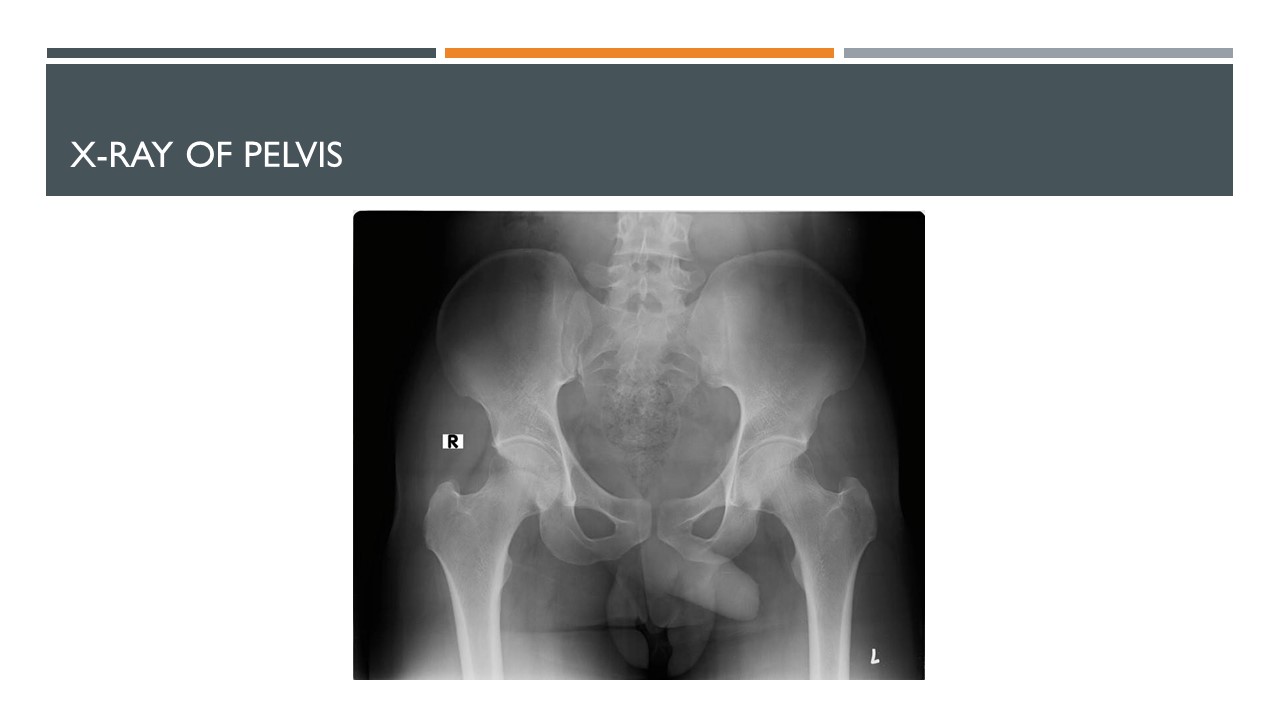

Thus in the presence of persisting enthesitis of heel, after excluding the possibility of post-traumatic enthesitis, it is important to rule out other differential diagnoses. The pain may be disabling and need attention and appropriate identification X-ray of the pelvis was done in the current case to exclude sacroiliitis (Fig 1.) X-ray of the heel of Achilles may indicate calcification at bony insertion suggesting enthesitis. Ultrasound examination or MRI imaging is recommended if associated tenosynovitis on neighbouring joints is suspected. Presence of conditions like hypercholesterolemia, hypothyroidism and other metabolic causes also needs be explored.

In the present case, the sacroiliitis was asymptomatic. The patient was HLA B 27 negative with normal inflammatory parameters. However, the patient cannot be categorised to have seronegative SpA, since he fulfilled the criteria of ESSG criteria only partially. The radiological features of sacroiliitis and enthesitis may assist in diagnosing ankylosing spondylitis in those who do not have inflammatory back symptoms. Although radiological features are present according to the New York criteria, the case cannot be categorized as AS since clinical features are absent. However, managing the patient with NSAID may help to improve the symptoms.